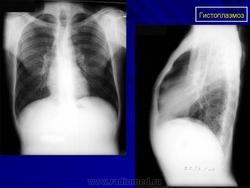

Продолжение.

Приложения:

1.g.slayd142.jpg2.g.slayd143.jpg3.g.slayd144.jpg

Рентгенологически выявляют крупно- и среднеочаговые тени в виде "ватных хлопьев", которые могут сливаться. В дальнейшем инфильтраты полностью исчезают или на их месте образуются очаги фиброза и кальцинации.

Хронический гистоплазмоз легких протекает в виде длительной прогрессирующей болезни, периодически дающей обострения. Наблюдается умеренная лихорадка, кашель с мокротой, при рентгенологическом исследовании выявляются каверны, фиброз и множественные кальцинированные очаги.